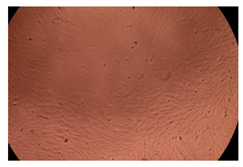

2.4. In Vitro Cytotoxicity Analysis

| Control |  |  | |

| Cop B | 10 µg/mL |  |  |

| 50 µg/mL |  |  | |

| 100 µg/mL |  |  | |

| Cop B/IMC = 10/1 (wt/wt) | 10 µg/mL |  |  |

| 50 µg/mL |  |  | |

| 100 µg/mL |  |  | |

| Cop B/Dorzolamide = 10/1 (wt/wt) | 10 µg/mL |  |  |

| 50 µg/mL |  |  | |

| 100 µg/mL |  |  | |